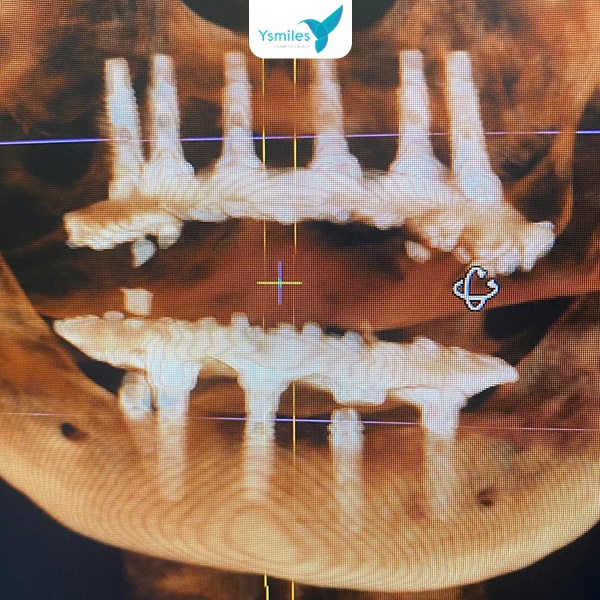

- Trang thiết bị công nghệ hiện đại: Việc áp dụng công nghệ hiện đại giúp ca trồng răng Implant diễn ra chính xác, an toàn và nhanh chóng hơn, kéo theo chi phí có thể cao hơn so với các cơ sở kém đầu tư về máy móc.

Chụp X-quang kiểm tra vị trí trụ Implant của răng

- Trang thiết bị hiện đại: Ysmiles liên tục cập nhật công nghệ chẩn đoán và điều trị chuẩn quốc tế, áp dụng công nghệ vào quy trình trồng răng Implant giúp đảm bảo tính chính xác và an toàn tuyệt đối.